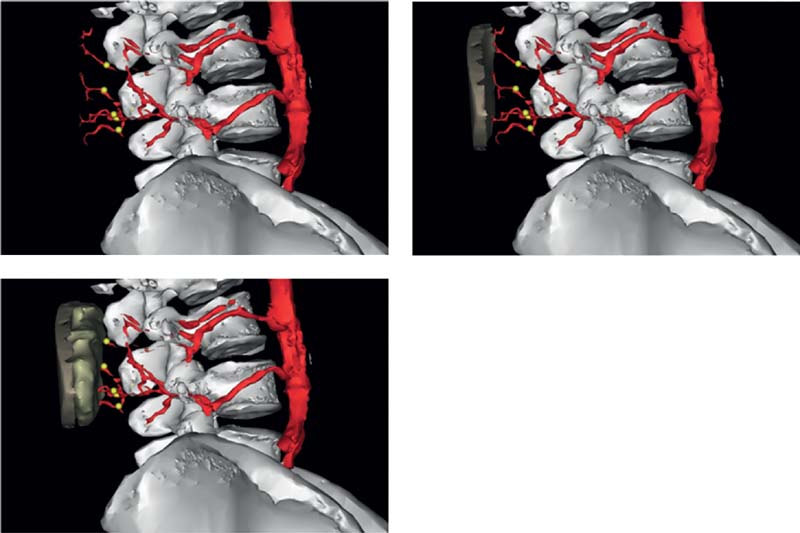

In a study of seven fresh cadavers injected with lead oxide, we performed three-dimensional (3D) angiography to capture the distribution, size, and course of the lumbar artery perforators, which arise from the paired lumbar arteries (L1, L2, L3, and L4)23 ( Fig. 8.2 ). Most pairs pass posterior to the quadratus lumborum, but some take a route through the muscle. The L1 to L3 arteries course between quadratus lumborum and the erector spinae muscles, whereas the L4 vessels generally pass anterior to quadratus lumborum. Once the lumbar arteries pass the lumbosacral fascia, they branch into smaller vessels supplying the lumbar integument. We observed that the individual perforator anatomy was quite variable, but in general the L4 perforators were often septocutaneous, whereas the L1 perforators were mostly musculocutaneous. Individual perforator anatomy was highly variable but septocutaneous perforators usually passed between the quadratus lumborum and erector spinae. Computed tomography angiography (CTA) shows the 3D course of lumbar artery perforators. More perforators arise from the L1 and L4 than from L2 and L3. Perforators measure ~1 mm in diameter where they penetrate the lumbosacral fascia ( Fig. 8.3 ).

Before surgery, the size, position, and course of the lumbar perforators is checked on a preoperative computed tomography (CT) or MRA scan. The patient should be positioned face down for the scan, so that the gluteal/lumbar perforators are not compresses. The X-axis is provided either by a horizontal radiopaque marker or by the height of the iliac crest ( Fig. 8.4 ). The lowermost lumbar perforator (L4), crossing the posterior iliac crest, is usually preferred to enable positioning of the scar as low as possible.